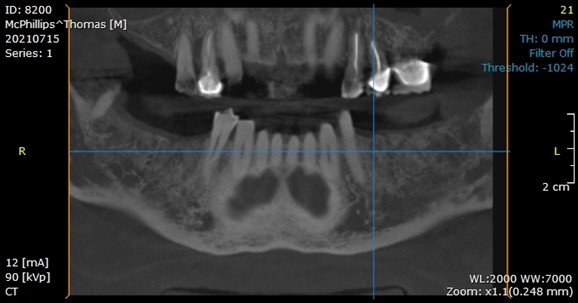

During the seventh-month appointment, a CBCT was taken to evaluate the bone-grafted site for implant placement.

At the eighth-month appointment, implants were placed in the #19, 20, 29, and 31 sites because the bone filled in nicely. Insertion torque was over 40 NCM for all implants. Healing screws were placed, and then we waited for osseointegration of the implants.